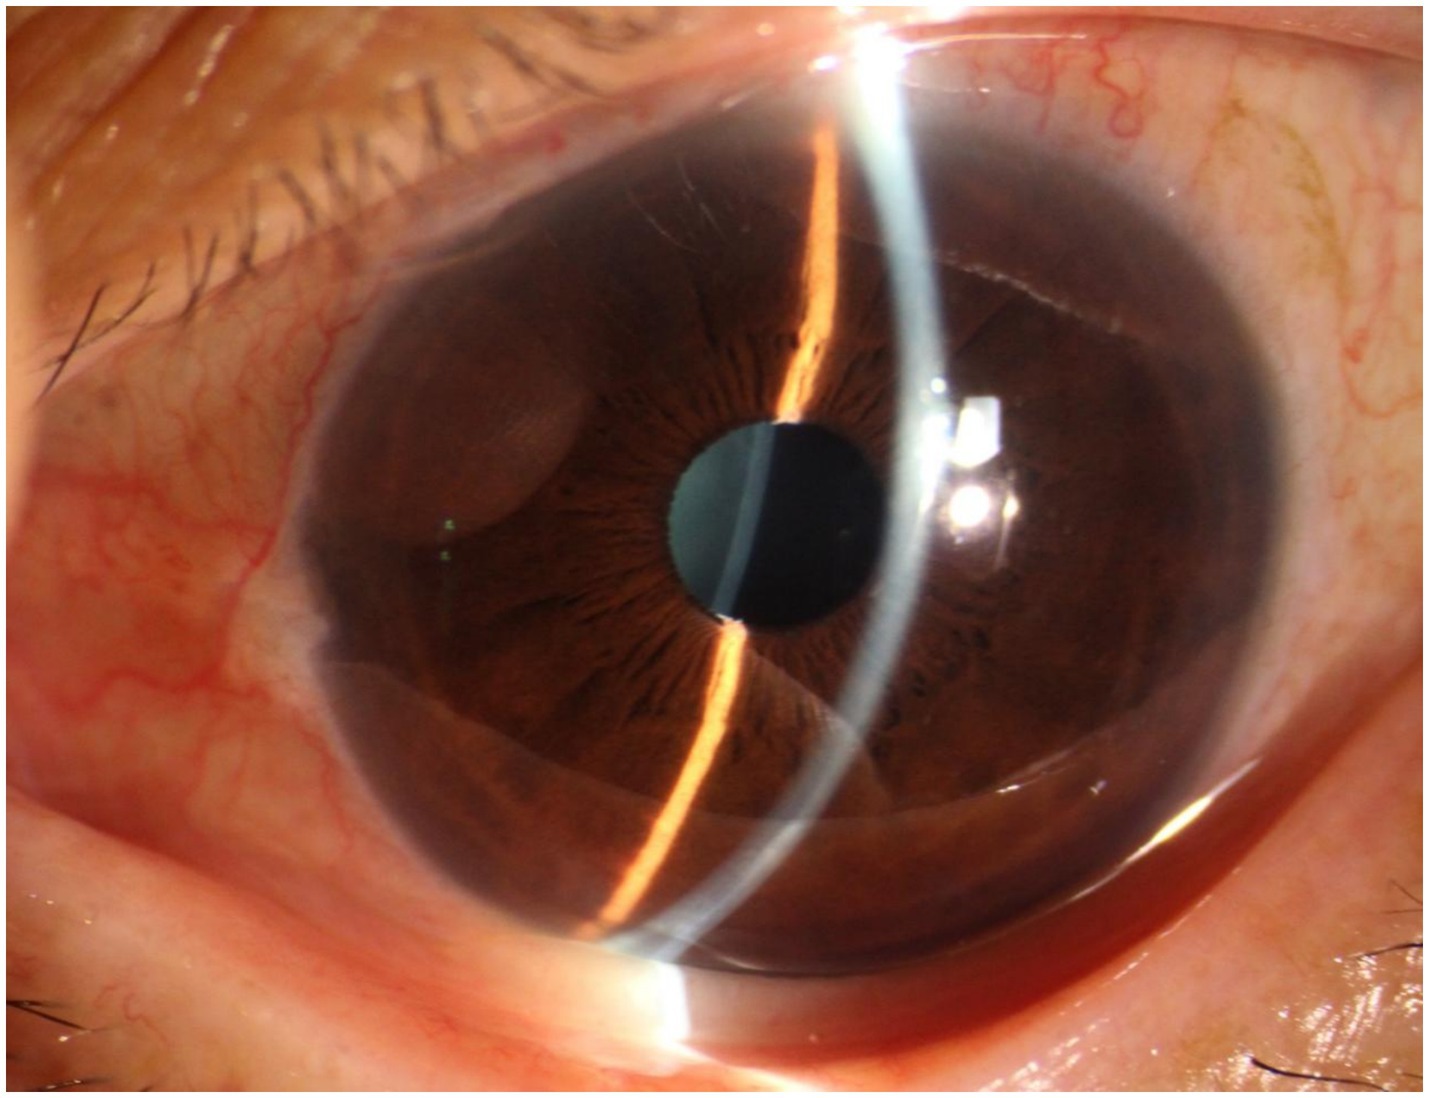

A 70-year-old Asian woman presented with left eye soreness and blurred vision for 1 month. When she first visited another hospital during this period, her visual acuity was 0.6 in the right eye and 0.1 in the left eye, with the intraocular pressure (IOP) being 15.2 mmHg in the right eye and 40.1 mmHg in the left eye, and she was diagnosed with left-eye glaucoma. Other ocular conditions at that time were unclear. She was treated with carteolol, brinzolamide, and pilocarpine eye drops for 1 month, but the therapeutic effect was unsatisfactory, so she visited our hospital. When the patient first presented to our hospital, the visual acuity of the right eye was 0.6, with an IOP of 17.1 mmHg, and that of the left eye was 0.6, with an IOP of 26.1 mmHg after using the aforementioned anti-glaucoma medications. The pupils of both eyes exhibited distinct miosis, likely caused by the medications. Considering that the patient was an elderly Asian female with an intumescent cataract, when we first saw her in the outpatient clinic, we initially thought the diagnosis was left-eye angle-closure glaucoma. However, we later discovered that the anterior chamber depths of both eyes were not shallow. It was not until we noticed unequal amounts of grayish-white debris on the pupillary margin of the left eye under the slit lamp (Figure 1). After careful consideration, we performed gonioscopy on the patient under topical anesthesia. We found that the angles of both eyes were open. Although this might have been due to the effect of pilocarpine, we also observed obvious pigment residues in the angles of the eyes (Figure 2). This alerted us to the possibility that the patient might have PEX. Ophthalmic evaluations were performed. Dynamic IOP monitoring revealed fluctuations of 17.1–20.1 mmHg in the right eye and 23.3–28.7 mmHg in the left eye despite treatment with two topical hypotensive agents. Fundus examination showed a red optic disc with a cup-to-disc (C/D) ratio of 0.4 in the right eye, whereas the left eye presented a pale-red optic disc with an increased C/D ratio of 0.7; both eyes had flat retinas with leopard-like fundus changes. Static perimetry (24–2 threshold test) demonstrated a visual field index (VFI) of 96% in the right eye (within normal range) and 66% in the left eye, with a superior arcuate scotoma in the left eye, classic for glaucomatous visual field loss. Optical coherence tomography (OCT) scans further confirmed: (1) in the right eye, no significant thinning of the macular neuroepithelial layer or ganglion cell layer (GCL), with only partial thinning of the retinal nerve fiber layer (RNFL); (2) in the left eye, partial thinning of the macular neuroepithelial layer, marked thinning of the GCL, and significant RNFL thinning—consistent with PEX-related glaucomatous optic neuropathy. Thus, based on the previous examinations, we dilated the pupils of both eyes. The dilation process was markedly difficult, which further strengthened our previous suspicion. Eventually, the anterior segment photographs after pupil dilation of both eyes are shown in Figure 3. We suspected that the development of the events was as follows: The grayish-white flakes on the periphery of the anterior lens capsule act like sandpaper on the iris, facilitating the release of a large amount of pigment from the iris. The released pigment will deposit and clog the trabecular meshwork (5). Upon detailed inquiry, the patient denied any relevant family history.

Figure 1. Anterior segment of the patient’s left eye. It can be observed that the anterior chamber depth is not shallow, and a small amount of fine grayish-white debris is visible on the round pupil.